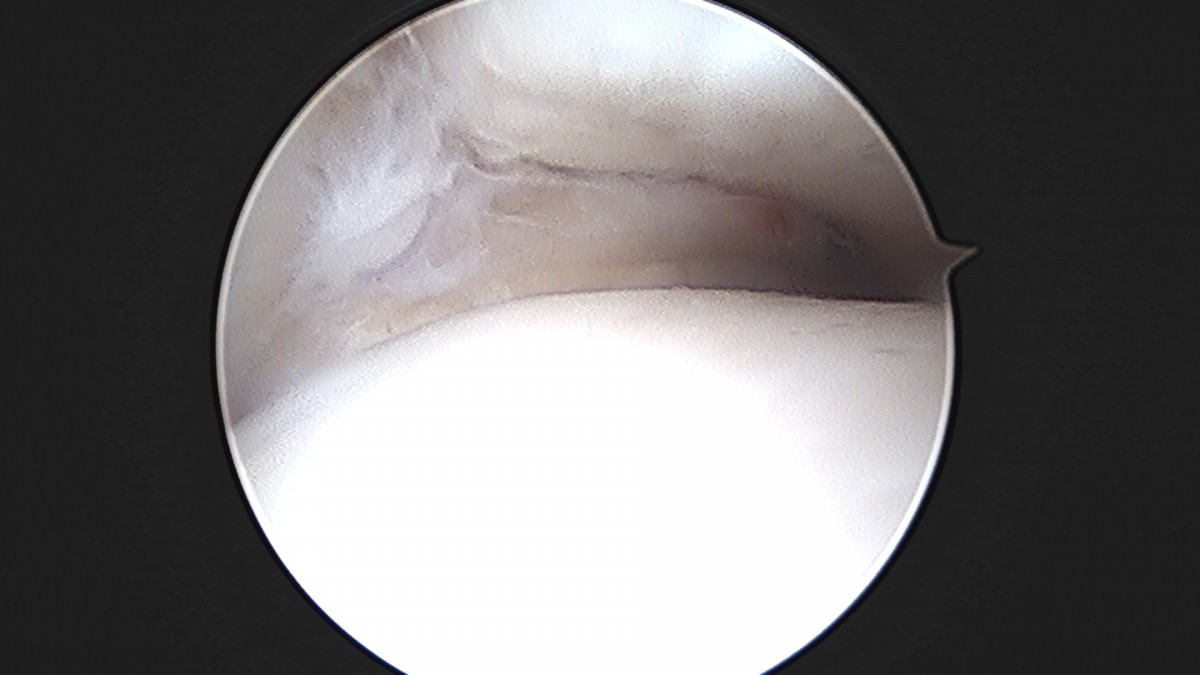

이재상원장님 발목 인대 봉합술 이지O 환자

작성자 최고관리자 댓글 0건 조회 681회 작성일 25-09-16 16:26